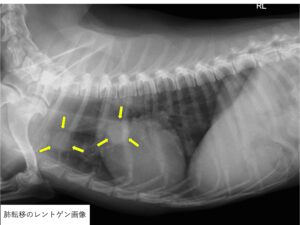

また、診断時には確認できなくても肺への転移を早期に起こすことが多く、腫瘍の転移によって亡くなる子が多いです。

身体検査にて腫れや疼痛が見られる骨や関節部位のレントゲン検査を実施します。

典型的なレントゲン所見としては骨の融解と骨髄の拡大、骨を覆っている骨膜が毛羽だった不整構造を示すようになるなどといった通称サンバーストと呼ばれる所見が見られます。

また、症例によっては腫瘍による病的骨折も確認されることがあります。

また、転移性病変の可能性やその時点での骨腫瘍の転移の有無を確認するために全身の精密検査を同時に行います。